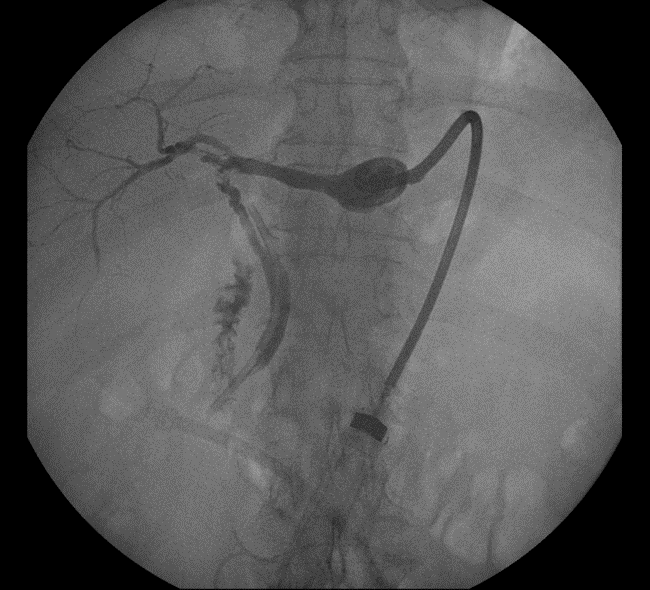

In the IR/GI suite the ERCP scope was advanced to the major papilla under general anesthesia. A glidewire was inserted into the CBD and then passed into the cystic duct. The wire was advanced through the cystic duct through the biloma and into the right posterior ductal system. The IR team had access to the intra-hepatic ducts already through the previously placed PTBD and they percutaneously advanced a snare under fluoroscopic guidance towards the endoscopist's wire to capture the wire and pull it back out the PTBD skin site (see Figure 5 for cholangiogram image). A PTBD was then advanced by IR over the guidewire into the duodenum (Figure 6) and secured into place. Final cholangiogram image showed contrast injected percutaneously traveling through the previous biloma without contrast extravasation and into the cystic duct and duodenum (Figure 7).

Figure 5. Cholangiogram image taken during combined IR/GI rendezvous procedure. An ERCP wire (thin arrow) was fed up through the cystic duct into the right posterior section, where PTBD was already in place. An IR snare (thick arrow) was used to capture the ERCP wire.